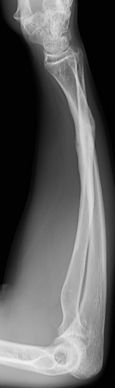

Se pueden tratar de forma conservadora en la mayoría de los casos mediante reducción y estabilización con un yeso braquio-antebraquial (3-5 semanas). La limitación en la pronación y supinación es la complicación más temida y se debe a consolidaciones viciosas, más frecuentes tras una fractura de antebrazo proximal (Figura 12).

Figura 12: a, b-Fractura metafiso-diafisaria distal tratada de forma conservadora donde se aprecia una consolidación viciosa con acortamiento del radio que limitaba la prono-supinación. c, d- Osteotomía correctora con aporte de injerto y osteosíntesis.